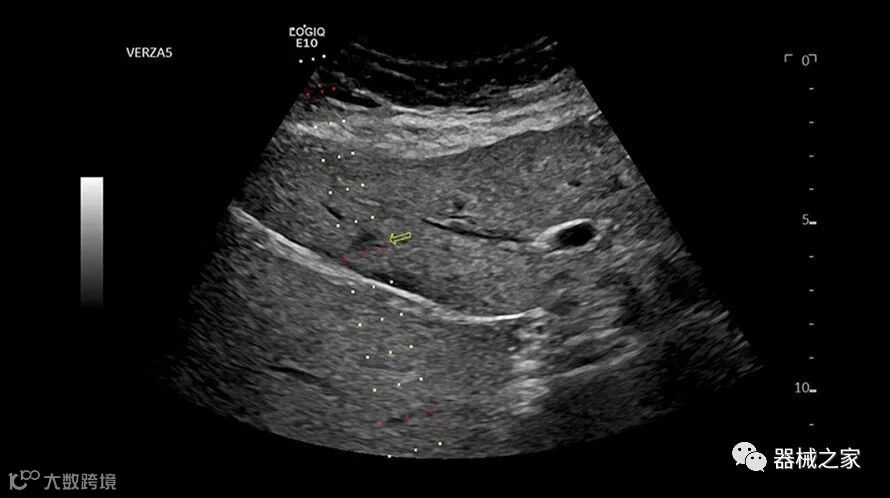

Baptist Health South Florida成为去年秋天西门子医疗保健公司Acuson Sequoia的首个商业安装网站。该系统将有助于增强胃肠病学,初级保健和减肥专业的成像能力。Sequoia可实现高分辨率成像,自动适应患者的体型和个人身体特征,有助于更加自信的诊断。它适应患者的组织密度,刚度和超声波束吸收的生物声学变化。这使得系统可以穿透高达40厘米而不会因衰减回波信号而导致图像质量下降。

Acuson Sequoia